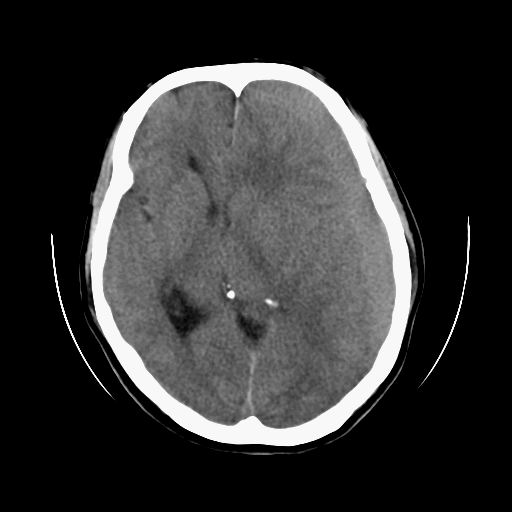

标题: CT13217:头部外伤三月余,头痛三天 [打印本页]

标题: CT13217:头部外伤三月余,头痛三天

左侧慢性硬膜下血肿

太典型,左侧慢性硬膜下血肿

左侧慢性硬膜下血肿,大脑镰下疝。

支持左额颞顶慢性硬膜下血肿伴大脑镰下疝。

血肿是急性、亚急性、还是慢性,要结合外伤时间考虑的,本例头部外伤三个月,应该是明显的慢性硬膜下血肿,但血肿的等密度显然不符合病理改变,估计是合并再次出血,中线结构移位明显,有脑疝形成。应穿刺减压。

血肿是急性、亚急性、还是慢性,要结合外伤时间考虑的,本例头部外伤三个月,应该是明显的慢性硬膜下血肿,但血肿的等密度显然不符合病理改变,估计是合并再次出血,中线结构移位明显,有脑疝形成。应穿刺减压。 大于2个月为慢性出血,2周到二个月为亚急性出血